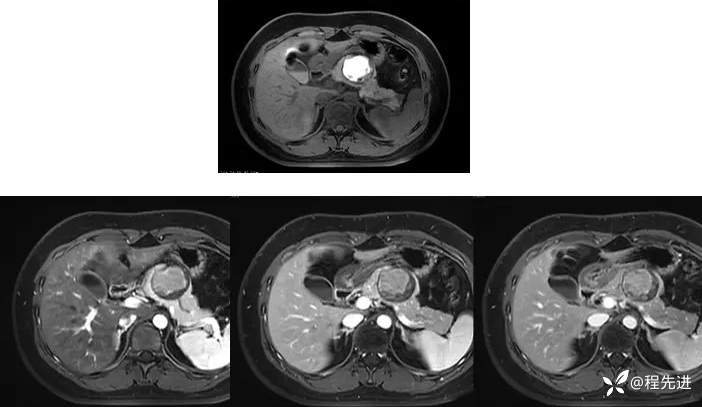

T1、T1+C: